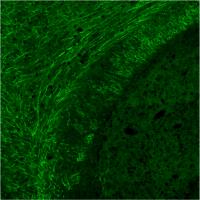

Myelin-producing brain cell with PLP protein stained in green